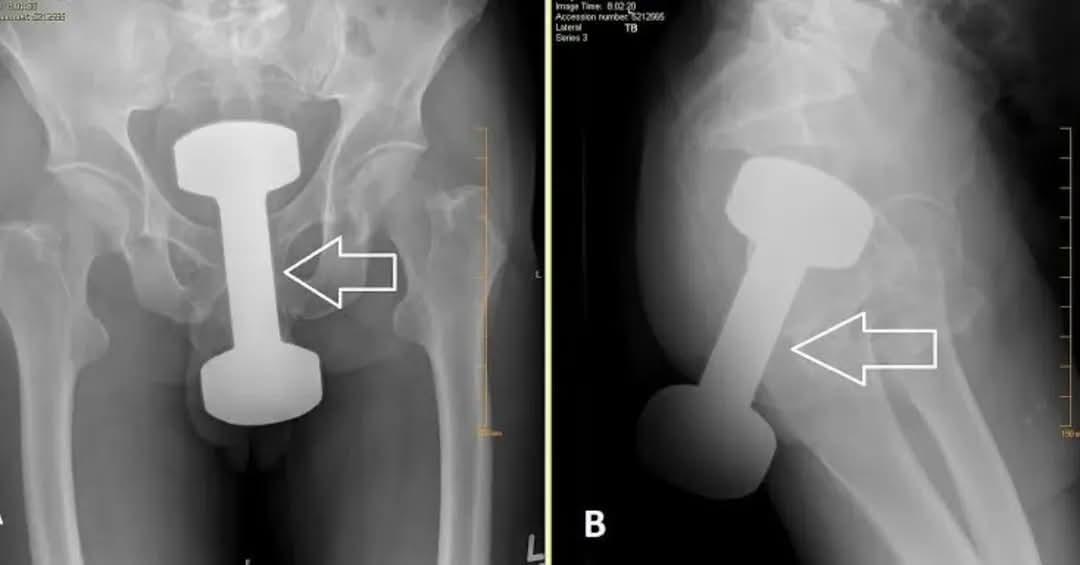

hip surgery xray